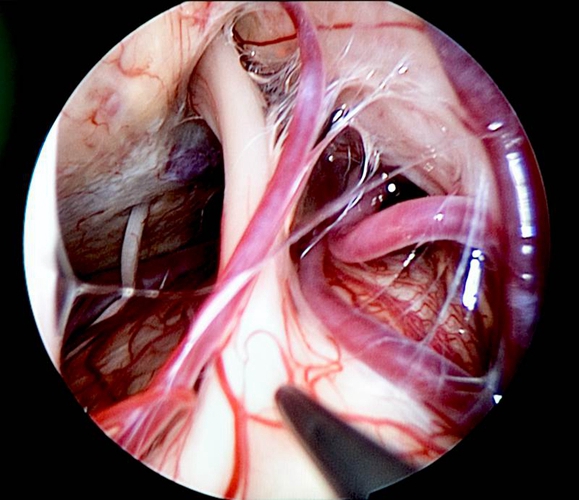

周圍性三叉神經痛

三叉神經微血管減壓手術